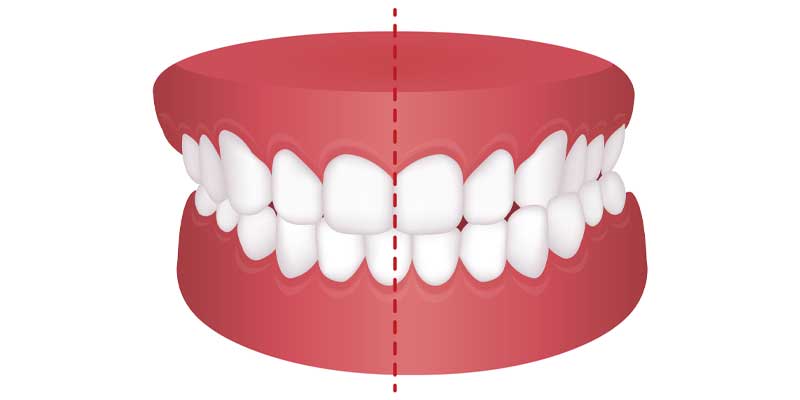

در حالت ایده آل، دندان های فک بالا باید کمی جلوتر از دندان های فک پایین قرار گیرند و با آن ها هم راستا باشند تا نیروهای فشاری به شکل مساوی توزیع شوند. اما در افراد دچار اختلال عرضی فک، این تناسب طبیعی به هم می ریزد. بخشی از دندان های فک بالا ممکن است داخل قوس دندانی پایین قرار بگیرند یا بالعکس. این اتفاق ممکن است در قسمت جلو دهان (کراس بایت قدامی) یا عقب دهان (کراس بایت خلفی) رخ دهد و حتی ممکن است فقط در یک سمت از دهان ایجاد شود.

انواع بایت های دندانی شامل وضعیت هایی مانند کراس بایت، اوربایت، اپن بایت، نرمال بایت، دیپ بایت، اورجت و آندربایت می شود. شناخت نوع دقیق بایت به تشخیص و درمان مؤثرتر کمک می کند. در برخی افراد، اختلال عرضی فک همراه با فک نامتقارن دیده می شود که موجب انحراف فک در حالت استراحت یا هنگام جویدن می شود.

- کراس بایت قدامی (جلویی): در این حالت، یکی یا چند دندان جلویی فک بالا هنگام بسته شدن فک ها، پشت دندان های فک پایین قرار می گیرند. این وضعیت شباهت هایی با آندربایت دارد اما معمولاً موضعی تر است.

- کراس بایت خلفی (عقبی): در این نوع، دندان های عقب فک بالا در موقعیتی قرار می گیرند که به جای اینکه بیرون تر از دندان های پایین باشند، داخل آن ها قرار دارند. این وضعیت ممکن است باعث انحراف فک به یک سمت هنگام جویدن یا صحبت کردن شود.

- کراس بایت یک طرفه و دوطرفه: اختلال عرضی فک ممکن است تنها در یک سمت از دهان (راست یا چپ) دیده شود یا هر دو سمت را درگیر کند.